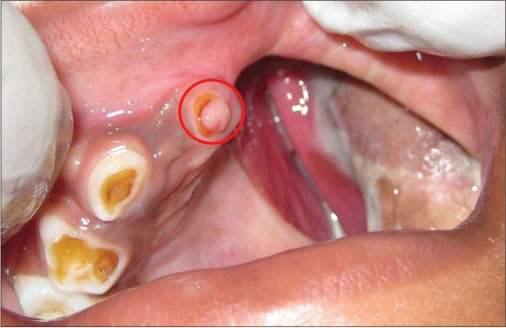

Intraoral examination revealed well-healed, skin graft-lined total maxillectomy defect on left side [Figure 1]. Deciduous canine and molars had erupted with evidence of erupting deciduous right central incisor. The existing obturator had become loose owing to infantile growth spurt. Eruption of deciduous teeth had rendered an incomplete seating of the obturator.

| Figure. 1 Intraoral view of well‑healed maxillectomy defect with red circle showing erupting deciduous incisor